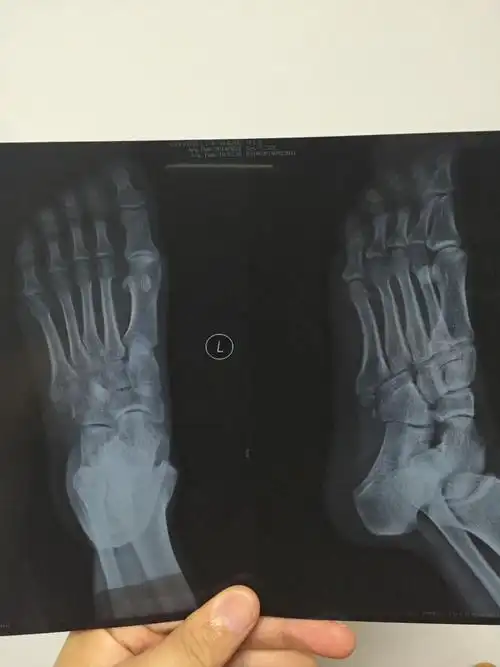

医院拍了个dr片子,诊断第五基底部骨折,然后医生说骨头已经在慢慢生长